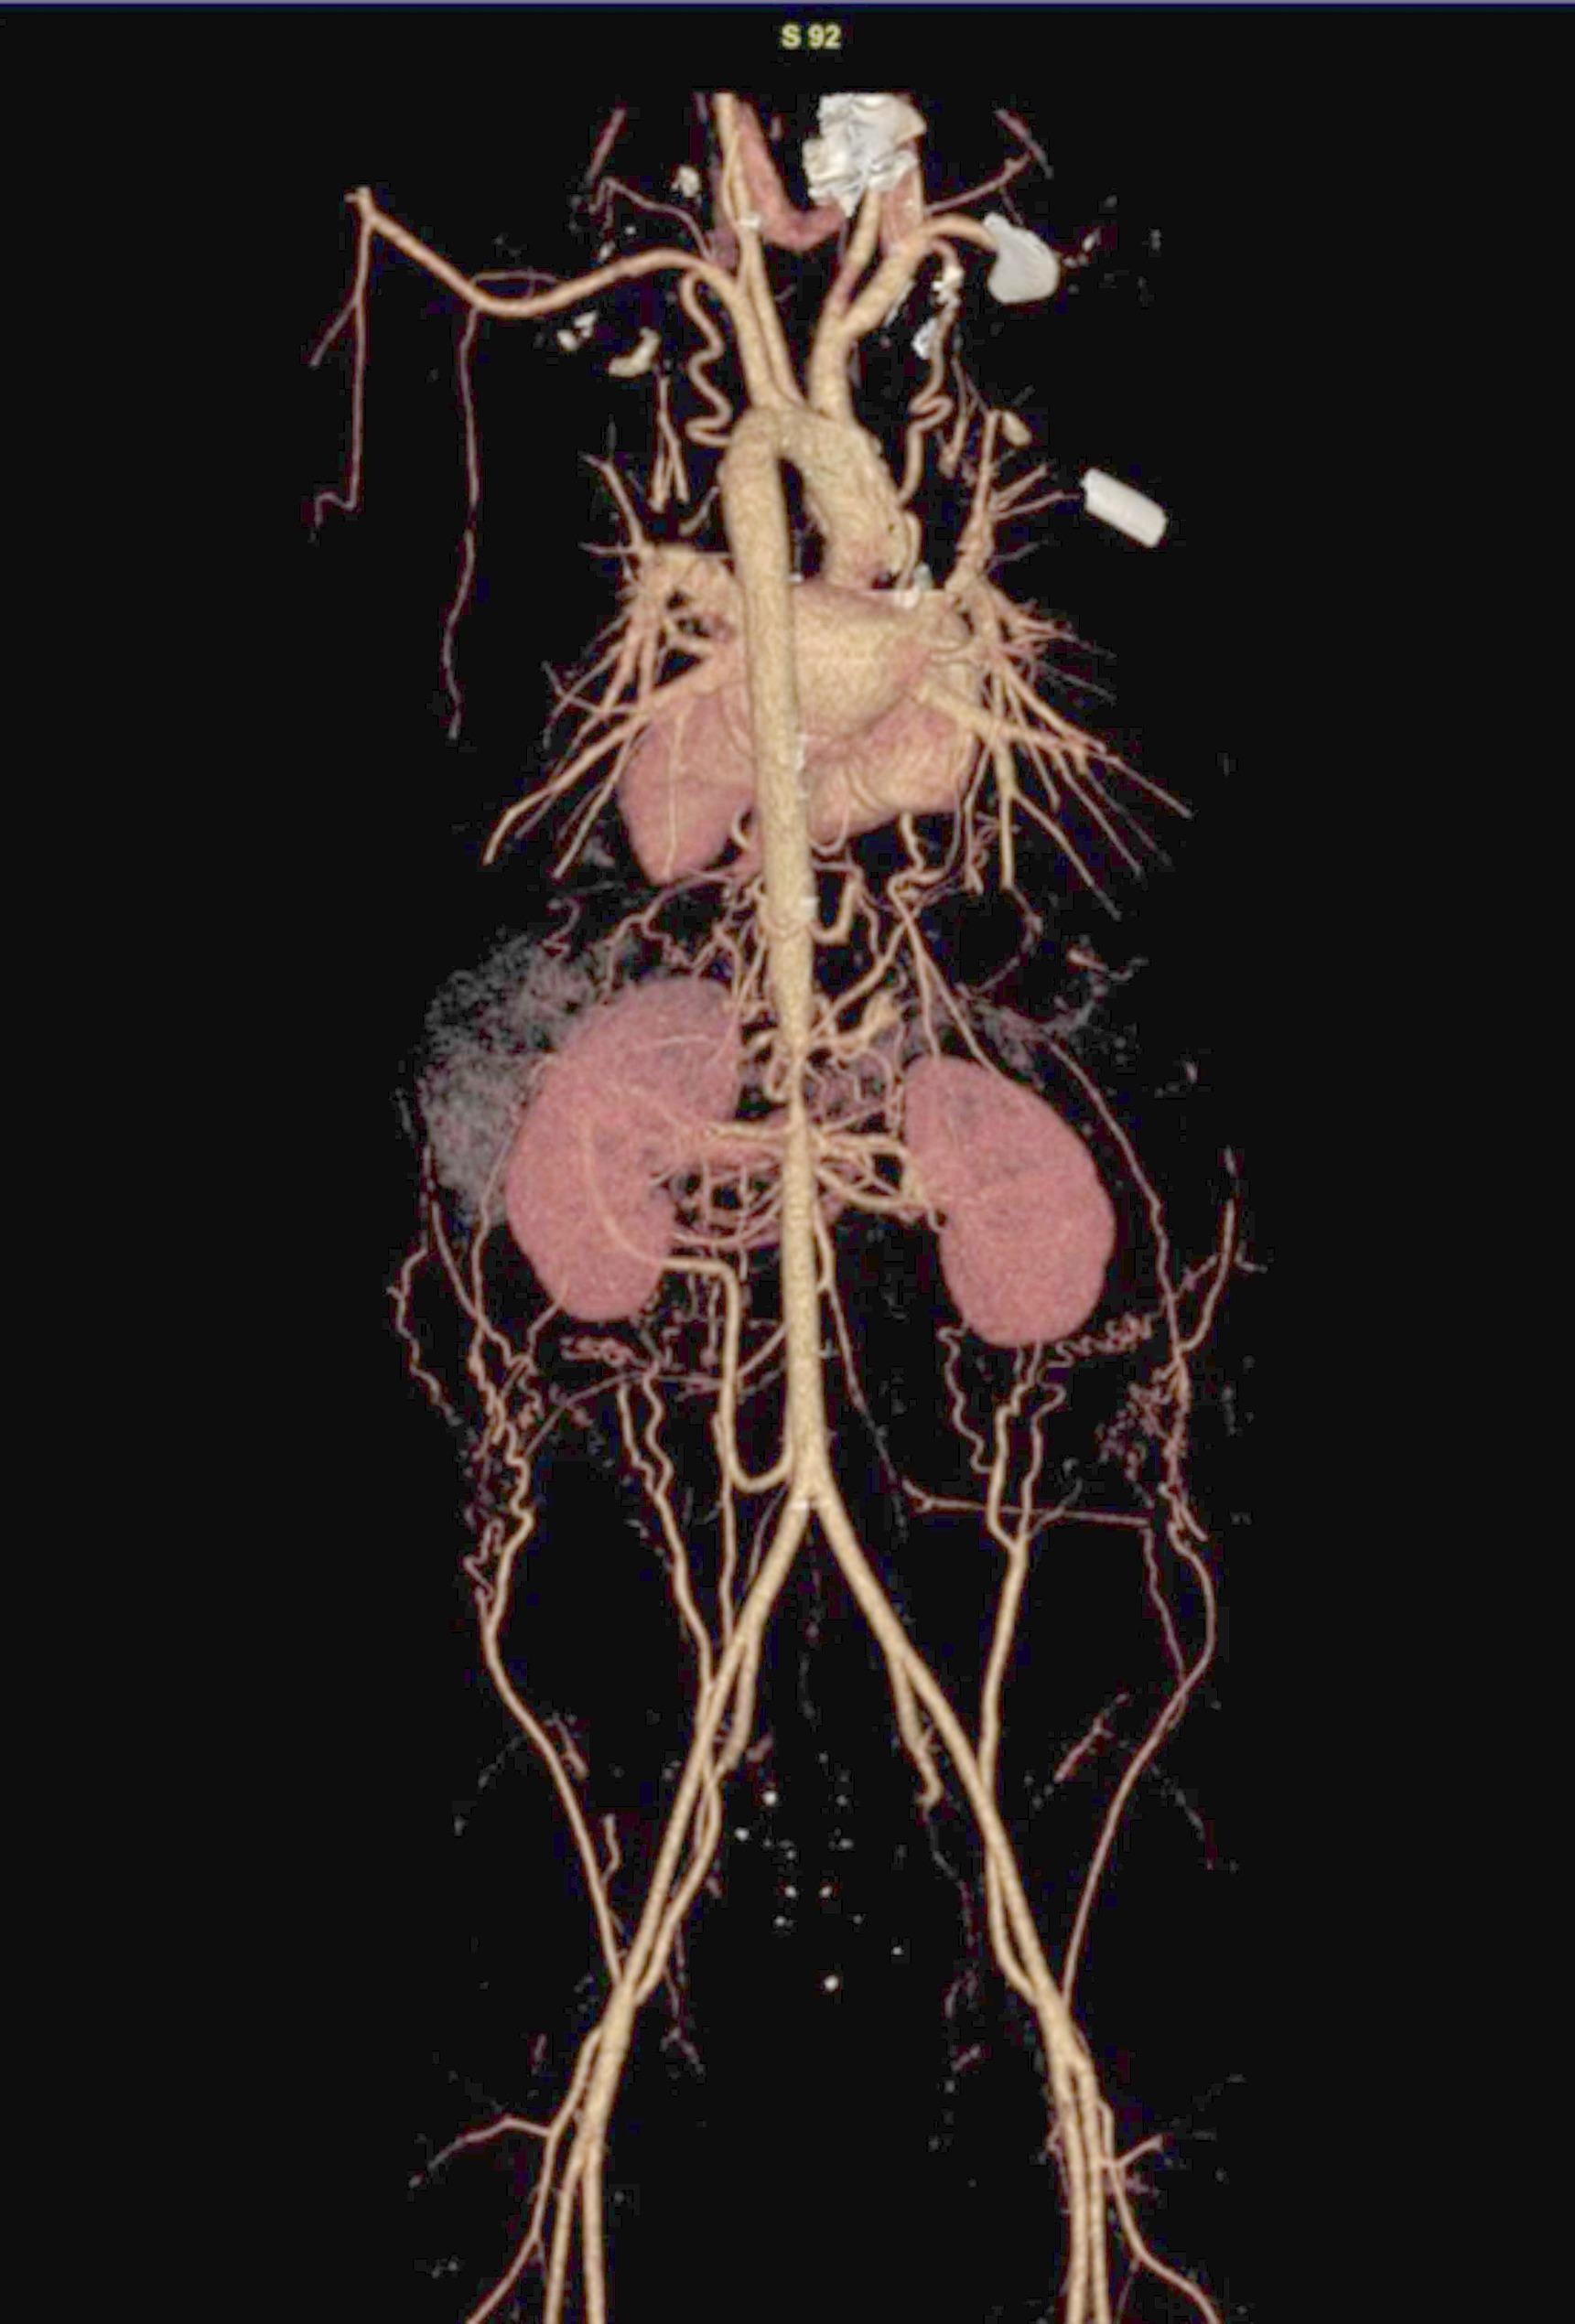

Case presentation: A 14-year-old male presented with a two-year history of refractory hypertension (peak:190/110mmHg) and exertional dizziness. Thoracoabdominal computed tomography angiography (CTA) revealed a focal coarctation (minimum luminal diameter: 4.2 mm, representing 70% stenosis) extending from the celiac artery origin to the superior mesenteric artery origin, without significant collateralization. Digital subtraction angiography (DSA)-guided balloon angioplasty (10 × 40 mm) resulted in a significant reduction of the transcoarctation pressure gradient from 45mmHg to 8mmHg, achieving normotension (120/80mmHg). At six-month follow-up, a 161% increase in aortic luminal diameter (to 11 mm) was observed, accompanied by complete regression of left ventricular hypertrophy (LVH), as evidenced by a decrease in interventricular septal thickness from 12 mm to 9 mm.

背景:先天性局灶性腹主动脉缩窄(CAAC)是一种罕见的血管畸形,常被误诊为中主动脉综合征(MAS)。管理CAAC的一个重大挑战,特别是在年轻人中,是在适应血管生长和发育的同时解决缩窄问题。本病例强调了多学科合作和成像引导的无支架球囊血管成形术在保持血管生长潜力方面的价值。病例介绍:一名14岁男性,有2年难治性高血压病史(峰值:190/110mmHg)和运动性头晕。胸腹ct血管造影(CTA)显示局灶性狭窄(最小管腔直径4.2 mm,狭窄70%),从腹腔动脉起源延伸至肠系膜上动脉起源,无明显侧支。数字减影血管造影术(DSA)引导的球囊血管成形术(10 × 40 mm)使血管收缩压力梯度从45mmHg显著降低到8mmHg,达到正常血压(120/80mmHg)。在6个月的随访中,观察到主动脉腔直径增加161%(至11mm),并伴有左室肥厚(LVH)的完全消退,室间隔厚度从12mm降至9mm。结论:无支架球囊血管成形术是治疗青少年CAAC的有效策略,既能立即缓解血流动力学,又能促进生长适应性主动脉重构。全面的主动脉造影对青少年难治性高血压的诊断和治疗至关重要。